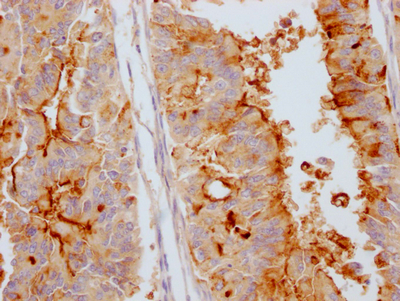

ApplicationELISA, IHC; Recommended dilution: IHC:1:50-1:200